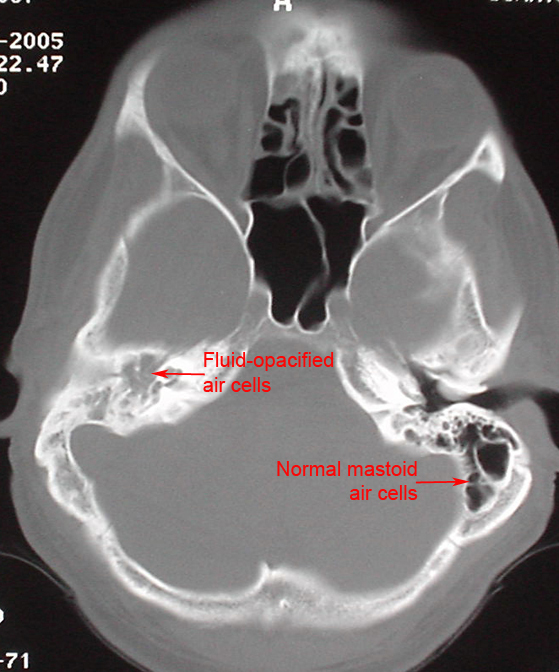

Mastoiditis

• CT initial investigation of choice

• Post-imaging contrast can be helpful to identify soft tissue complications or vascular complication such as dural venous thrombosis

• Partial to complete opacification of mastoid air cells, sometimes the middle ear cleft as well

• Erosion of the mastoid air cell bony septum may be present